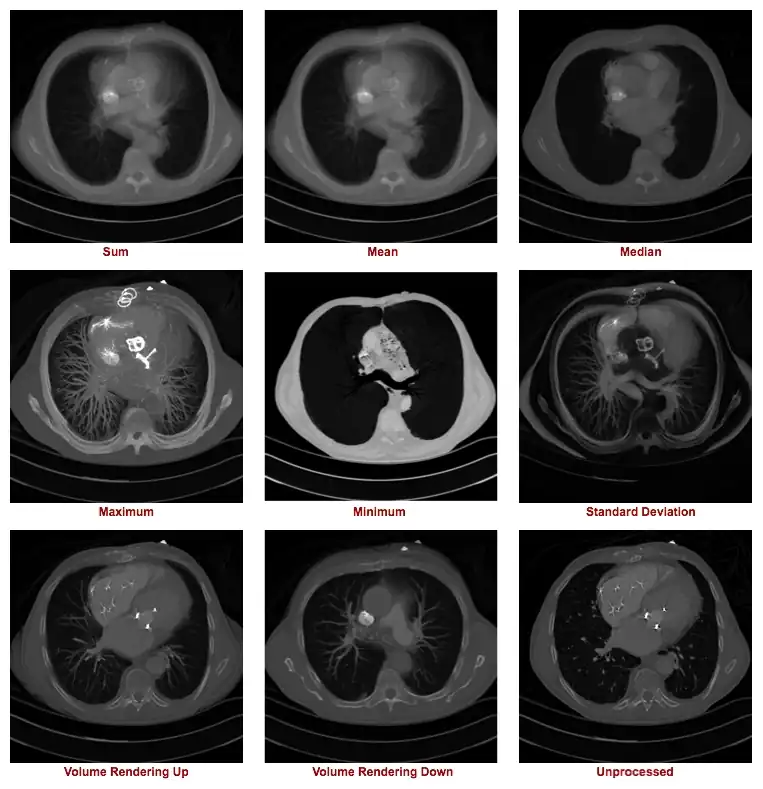

- Figure 5.14 illustrates the outcome of a range of z-projection methods, with a single slice shown in the bottom right hand corner for reference purposes. The first image in the top left shows the result of summing 16 slices, and the other two images on that row show the results of computing the mean and median of these slices.

- The first two images in the second row show the result of what are called a Maximum Intensity Projection (MIP) and a Minimum Intensity Projection (MinIP), respectively. A MIP evaluates each voxel along each line of voxels through the volume to determine the maximum voxel value and forms an image using the values so determined for each line. A MinIP uses the minimum voxel values, as illustrated in Figure 5.15.

- The outcome of this form of processing is the generation of an image which includes visual depth cues on the basis that similar voxel values will be displayed with a similar transparency and those closest to the reference slice having a stronger contribution than those from more distal slices. Further, note that all voxel values in each line contribute to the rendered image, in contrast to the limited number of voxels that contribute to a MIP or a MinIP image. A 3D effect results from volume rendering, as illustrated in Figure 5.14.

- Notice that volume rendering can be applied from distal to proximal slices, as illustrated in our figure, as well as in the opposite direction, i.e. from proximal to distal slices. Hence the terms Volume Rendering Up and Volume Rendering Down used in Figure 5.14.

- The type of axial projection method appropriate to an individual patient study is dependent on the anatomical and/or functional information of relevance to the diagnostic process. Let's take the case of imaging contrast-filled blood vessels, for example, in our nine example images above. Note that a MIP can be used to give a visually-stunning impression of the vessel bed in the patient's lungs. There's little depth information in this projection, however, so that overlapping and underlying vessels can obscure lesions that might be present in blood vessels of interest. The application of this form of axial projection to angiography is therefore limited to studies where vessel overlap isn't an issue. The inclusion of voxel transparency and depth weighting in volume rendered images addresses this limitation of MIP processing.